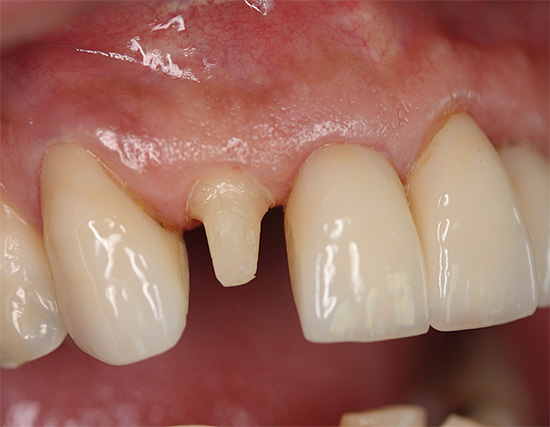

A volte ci sono casi in cui è necessaria la rimozione del nervo dopo una grave lesione del dente, molto spesso quella anteriore. Pulite traumatica Non è così comune come la polipite infettiva di origine cariosa, ma sarà comunque necessario rimuovere il nervo dal dente.

Buon pomeriggio In caso di infortunio, ha rotto 3 denti anteriori (2,1 a 1/2 dell'altezza era rotta, 1,1 e 2,2 - schegge parziali). Il dente 2.1 è stato depolpato, il canale è stato riempito 5 giorni fa. Inoltre, il dentista consiglia di aggiungere questo dente al perno. 1.1. e 2.2 sono estesi, non danno particolare fastidio, c'è un leggero disagio con la pressione e si verifica periodicamente un leggero dolore "doloroso". Il dentista afferma che potrebbe essere necessario depulpare e altri 2 denti. Quanto è necessario nel mio caso?

Benvenuti! Le informazioni più precise (obiettivo) sono fornite dall'EDI del dente. Non tutte le cliniche hanno un dispositivo corrispondente. Quando si determina l'eccitabilità elettrica della polpa, è possibile scoprire se c'è un processo infiammatorio di insorgenza o meno. Con lesioni di questa forza, è spesso necessario avere un dente dentellato. Non penso che questa sia una grande tragedia, poiché con una certa esperienza e professionalità di un medico puoi correggere le imperfezioni di un sorriso, se ciò accade (forma dei denti cattivi, lievi curve, curve, colore naturale dei denti insoddisfacente, lunghezza della corona dei denti, ecc.) . Cioè, ci sono spesso anche vantaggi dal restauro, ma la domanda, ancora una volta, è se rendere il dente "morto"?

Se la polpa è morta per EDI, quindi senza trattamento dei canali, il dente può essere portato a parodontite, periostite e altre complicazioni purulente da cui il viso si gonfia. Se la polpa è sana dall'EDI, allora c'è la possibilità di cavarsela con il restauro senza perni.